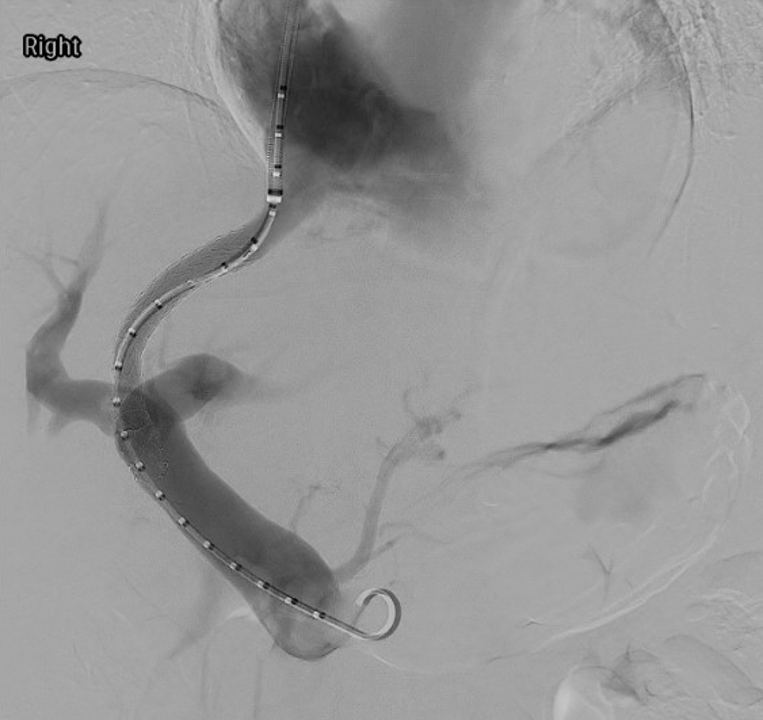

TIPS database at UMass Chan

TIPS is a potentially life altering procedure for patients with chronic liver disease and associated portal hypertension. We are keeping a TIPS database of all patients here at UMass Chan who have undergone a TIPS procedure for QA and clinical outcome research projects.